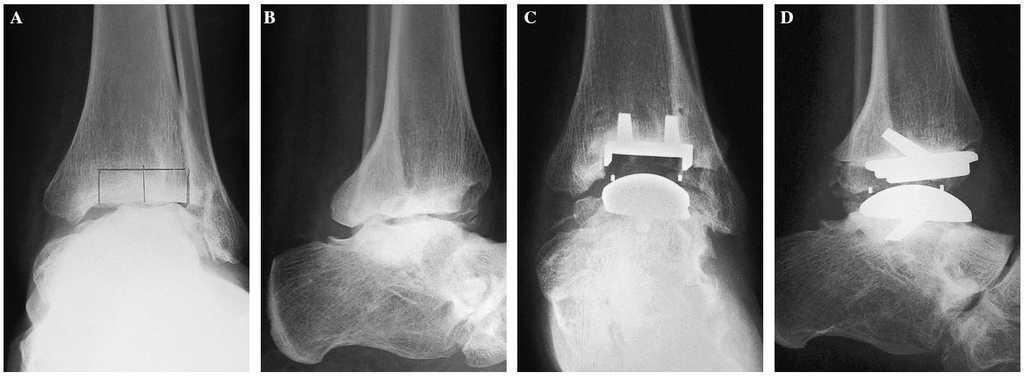

Figura 6. (Izquierda) Paciente con artrosis primaria de tobillo. (A) Radiografía anteroposterior y lateral. (B) Control radiológico de los implantes, anteroposterior y lateral . (Derecha) Secuelas de una fractura de pilón tibial. (C) Imagen preoperatoria. (D) Control radiográficio del implante.